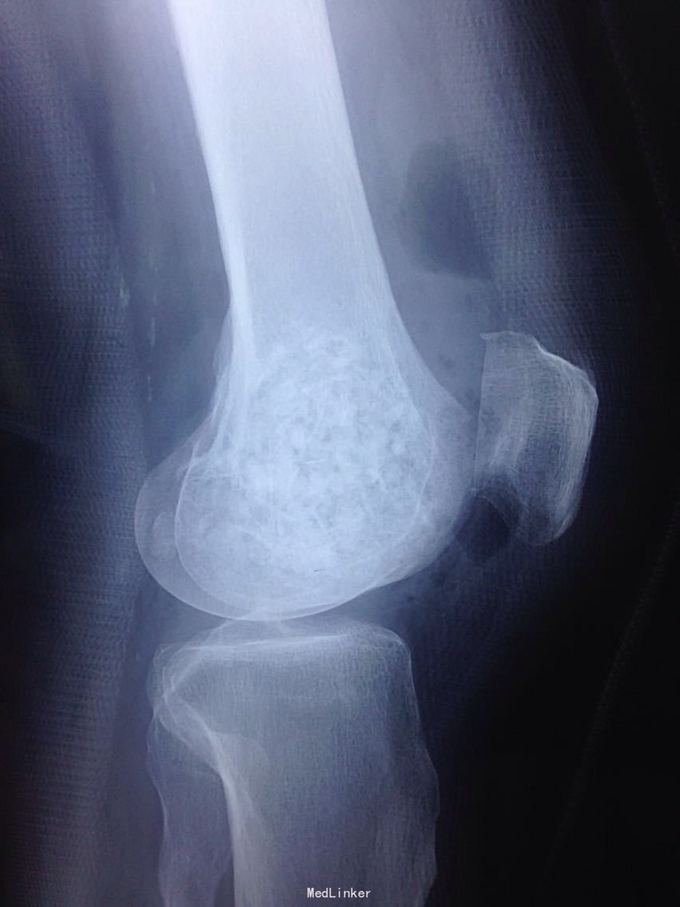

男性51岁,左膝关节疼痛不适10余年。因症状较轻,不影响活动,未曾系统诊治。一月前因扭伤致疼痛加重,拍片检查,见股骨远端骨质异常,进一步行CT示股骨髁占位病变,考虑骨囊肿。既往有高血压,糖尿病病史。近期无低热,体重下降。

诊断:左股骨远端占位 因皮质完整,行手术开窗刮除,自体髂骨及同种异体骨混合植骨填充治疗。切取组织送病理检查

刮除占位组织如图所示,送病理检查了,结果还没回来。 没有全身症状,像是原发灶,骨皮质完整,没有明显骨膜反应请专家们看看,什么可能性比较大? 补上病理结果和术后片子